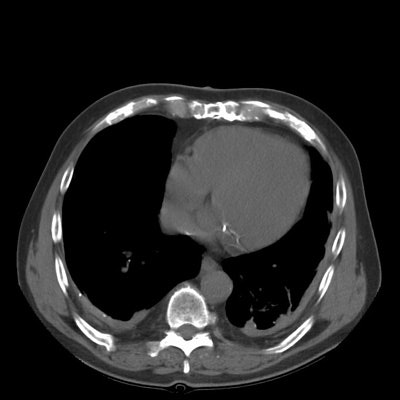

Rounded atelectasis:

The images show bilateral posterior pleural thickening. Within the left posterior lung a rounded pleural based mass-like opacity into which lung markings radiate can be identified. The left major fissure is displaced posteriorly. The lesion has remained stable for many years. The findings are consistent with rounded atelectasis. (Click small images to enlarge)